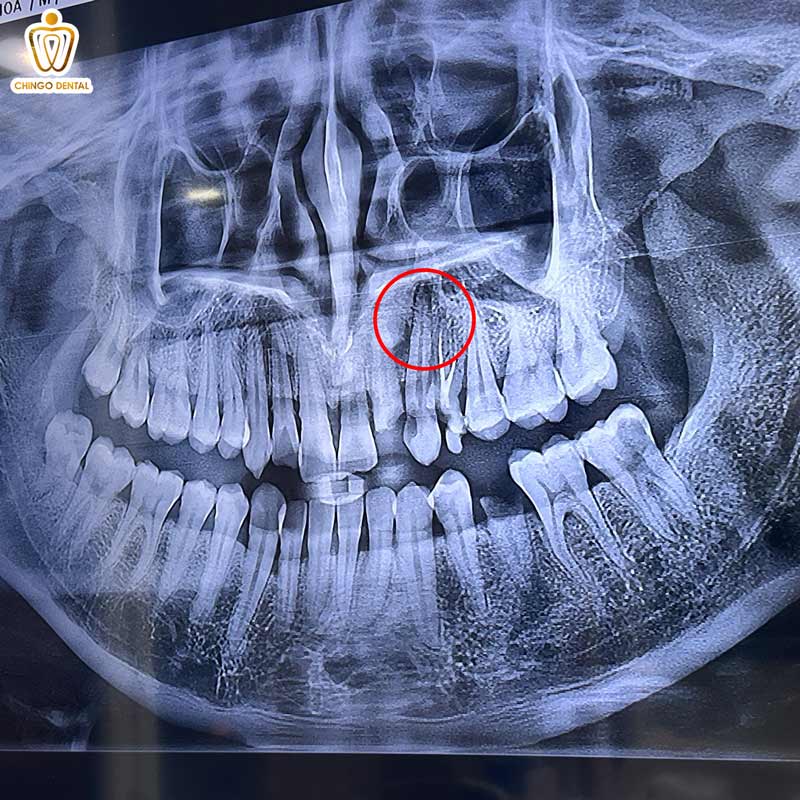

X-quang: Tổn thương thấu quang lớn, giới hạn rõ, bao bọc thân (crown) của răng ngầm và đẩy răng đó ra xa vị trí mọc bình thường.

| Hình ảnh X-Quang | Tổn thương thấu quang (đen) hình tròn/oval, giới hạn rõ, liên tục với màng xương răng quanh chóp. | Tổn thương thấu quang bao quanh cổ răng và thân răng ngầm. Hình ảnh “quần sáng” ôm lấy thân răng. | Tổn thương thấu quang, có xu hướng phát triển theo chiều trước – sau dọc theo xương hàm. Có thể có vách ngăn mỏng (đa buồng). |

Nang thân răng là gì? Đây là một loại nang trong xương hàm, có đặc điểm là bao bọc một phần hoặc toàn bộ thân của một chiếc răng chưa mọc (răng ngầm) hoặc răng thừa ngầm. Nang dính vào răng ở vị trí tiếp nối men – cement (cổ răng). Thường gặp nhất ở răng khôn (số 8) và răng nanh.